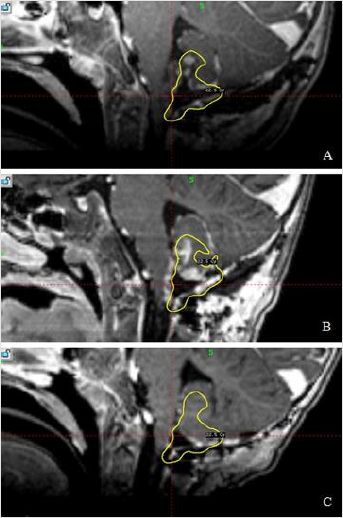

After 2 months patient showed an improvement of rightside hemiparesis. MRI examination revealed that the previously found contrast-enhancing lesions in the posterior fossa were no longer detectable, linear enhancement around the brain stem was decreased (Figure 3). However, there were multiple spinal intradural lesions. Therefore, the patient underwent additional chemotherapy and radiotherapy. 9 months after treatment, MRI examinations showed progression and new metastasis along the spinal canal: the cervical spine and thoracolumbar segments. However, no new metastasis or progression was detected in the area treated with hypofractionated stereotactic radiosurgery.

Figure 3: A) Postoperative MRI. B) MRI before stereotactic radiosurgery. C) MRI 2 months after the second surgery. Previously found contrast-enhancing lesions in the posterior fossa were no longer detectable, linear enhancement around the brain stem decreased. Yellow line marks 55% isodose.